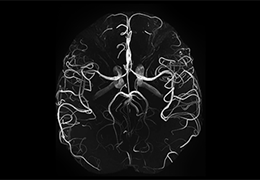

Eclipse 成像智能功能提供强大的处理能力和最佳质量的影像,同时减少质量错误并提高剂量效率。

凭借 AI、专有算法和先进的影像处理能力,提供出色的影像质量和无与伦比的诊断信心。

提供相配视图选项,以减少所需的曝光次数,并提供更清晰的感兴趣区域视图。